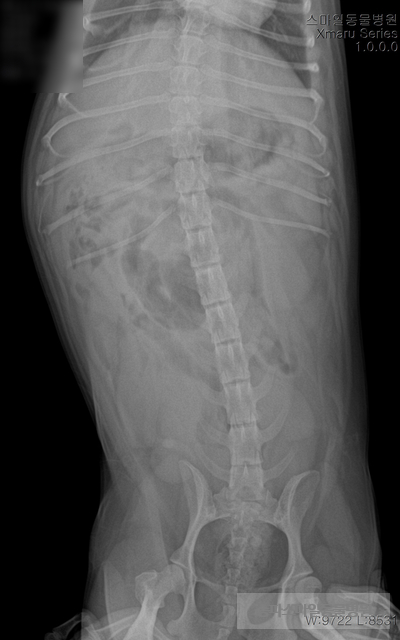

초음파 검사상 자궁의 크기가 매우 확장되었으며 자궁 내부의 액체가 고여있는 것으로 확인되었습니다.

강아지 자궁축농증이 진단되었습니다.

수액처치후 “ㄹ” 긴급수술 하였습니다.

수술은 안전하게 마무리되었습니다.

자궁 내부는 곪아 있었습니다.